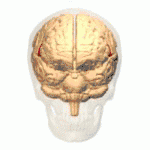

(A) CT scan of a patient with middle cerebral artery stroke illustrating hypodensity areas within the temporal and frontal lobes. (B) CT scan displaying an ischemic stroke bordering the fronto-parietal opercular cortex (red arrow) and a left-sided ichemic lesion of the fronto-parietal opercular cortex (blue arrow).

CT scan

This computer-tomography type of imaging is one of the most used in any clinical environment and although it can detect some of the brain areas affected by a stroke or a trauma it does not provide the same acuity as the magnetic resonance imaging. CT scans can also reveal, in patients with the syndrome, the bilateral cortical infarcts located in the posterior frontal region involving the opercular areas.[3]